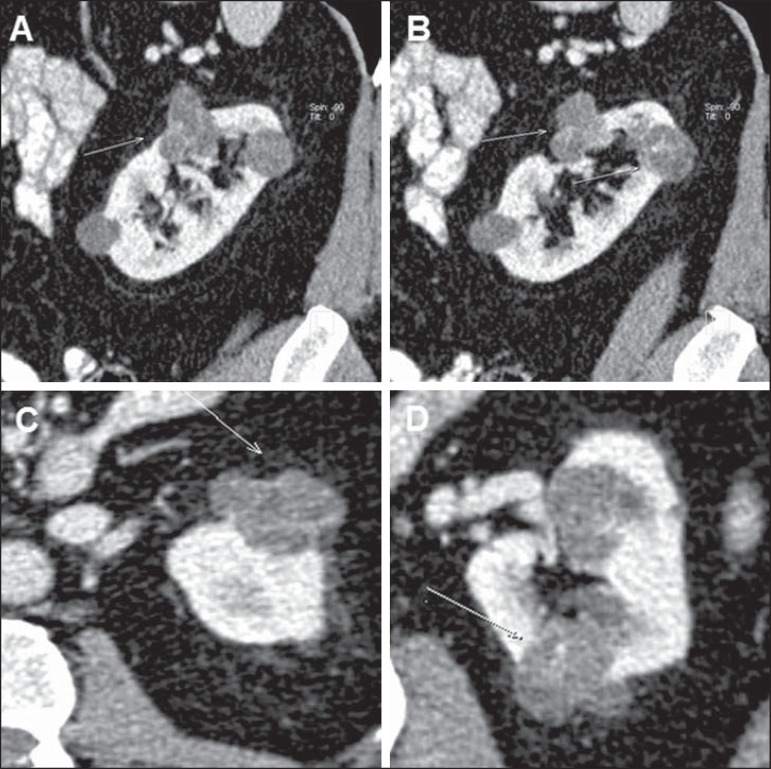

Figure 7.

Bosniak category III. MDCT images, axial (A,B,C,E) and coronal (D,B) demonstrating a hyperattenuating mass in the left kidney, with peripheral Gross calcifications (arrow on E). Indeterminate cyst.

Lesions in this category are cystic neoplasms which may present imaging findings similar to those of category III (wall thickening or gross and nodular septal thickening), but contrast-enhanced solid components are still observed adjacent to the lesion wall or septa(1,9) (Figures 8 and 9). Until proven otherwise, such lesions are considered renal cell cancer with eminently surgical indication, since they are malignant in 95-100% of cases(9,10).

Figure 8.

Bosniak category IV. MDCT images, sagittal (A,D) and axial (B,C) reconstructions demonstrating a cystic lesion with gross and nodular parietal thickening.

Figure 9.

Bosniak category IV. MDCT images, sagittal (A,B) and axial (C,D) reconstructions demonstrating lobulated cystic lesions with contrastenhanced, thickened septa.